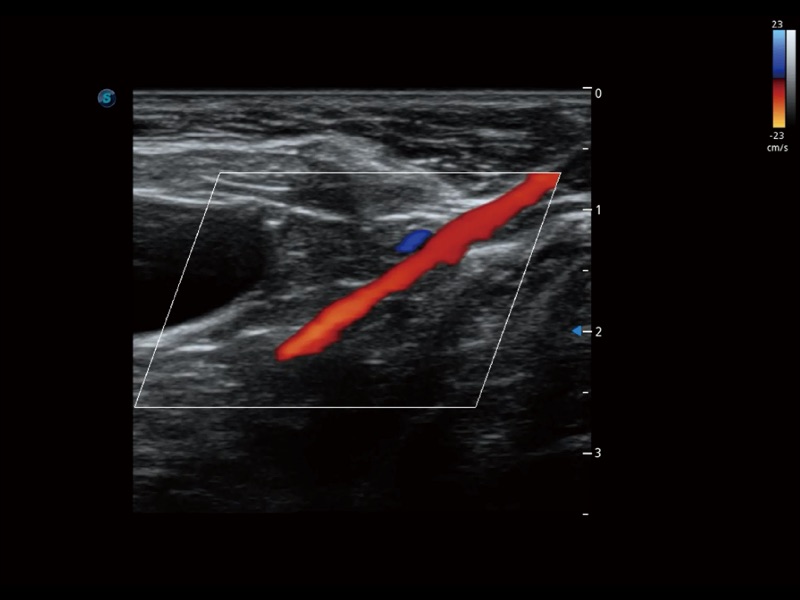

大型犬、马科、农场动物及大型异宠动物

通过创新的 Matrix E自适应滤波器和超长时间域算法,极大提升超低速微细血流的检出能力,同时更精准地滤除软组织和噪声信号,为兽用医生提供以往无法通过常规血流获得的疾病诊断信息。

通过色彩血流和实时宽景相结合,可观察到完整的静脉或动脉的血流,方便医生检查。实时扫查过程中,如有任何操作失误也可以很容易地进行回扫擦除,而不会中断扫查。

ProPet 70 全新的动物超声智能软件和丰富的探头群,为动物医生提供了高清晰度和精细分辨率的图像,无论在宠物、马科、畜牧还是实验室动物等应用中都可以轻松应对,为您的日常工作带来满意的体验。